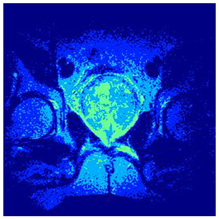

Table 5 presents the segmentation of the MRIs using EO for a qualitative inspection. From Figure 5, it is clear that two lumps in the prostate have been highlighted by the thresholding process. Prostatic MRIs present noisy conditions, which makes it difficult to visualize the thresholding with the naked eye, so in Figure 5 we present the thresholded image as well as the histogram with the values of the thresholds generated by the EO. It can be observed in the histogram that the thresholds present an adequate distribution, even though this particular image has impulsive noise and a simple shape. Our findings indicate that four thresholds are typically sufficient for this application, which corresponds to identifying five different tissue types in the image. A smaller threshold value may result in a lack of sufficient contrast to highlight relevant anatomical structures, such as the prostate capsule. In contrast, a higher number of thresholds may lead to the incorrect differentiation of anatomical regions that should be connected.

Table 5.

Segmentation of transaxial-cut prostate MRI images Using EO and cross-entropy. This table presents the segmentation results of transaxial-cut prostate MRI images using the equilibrium optimizer (EO) and cross-entropy. Each row corresponds to a distinct MRI image, while the columns nt represent the number of thresholds applied during segmentation. The results illustrate the performance of the EO algorithm across different threshold levels for each image.